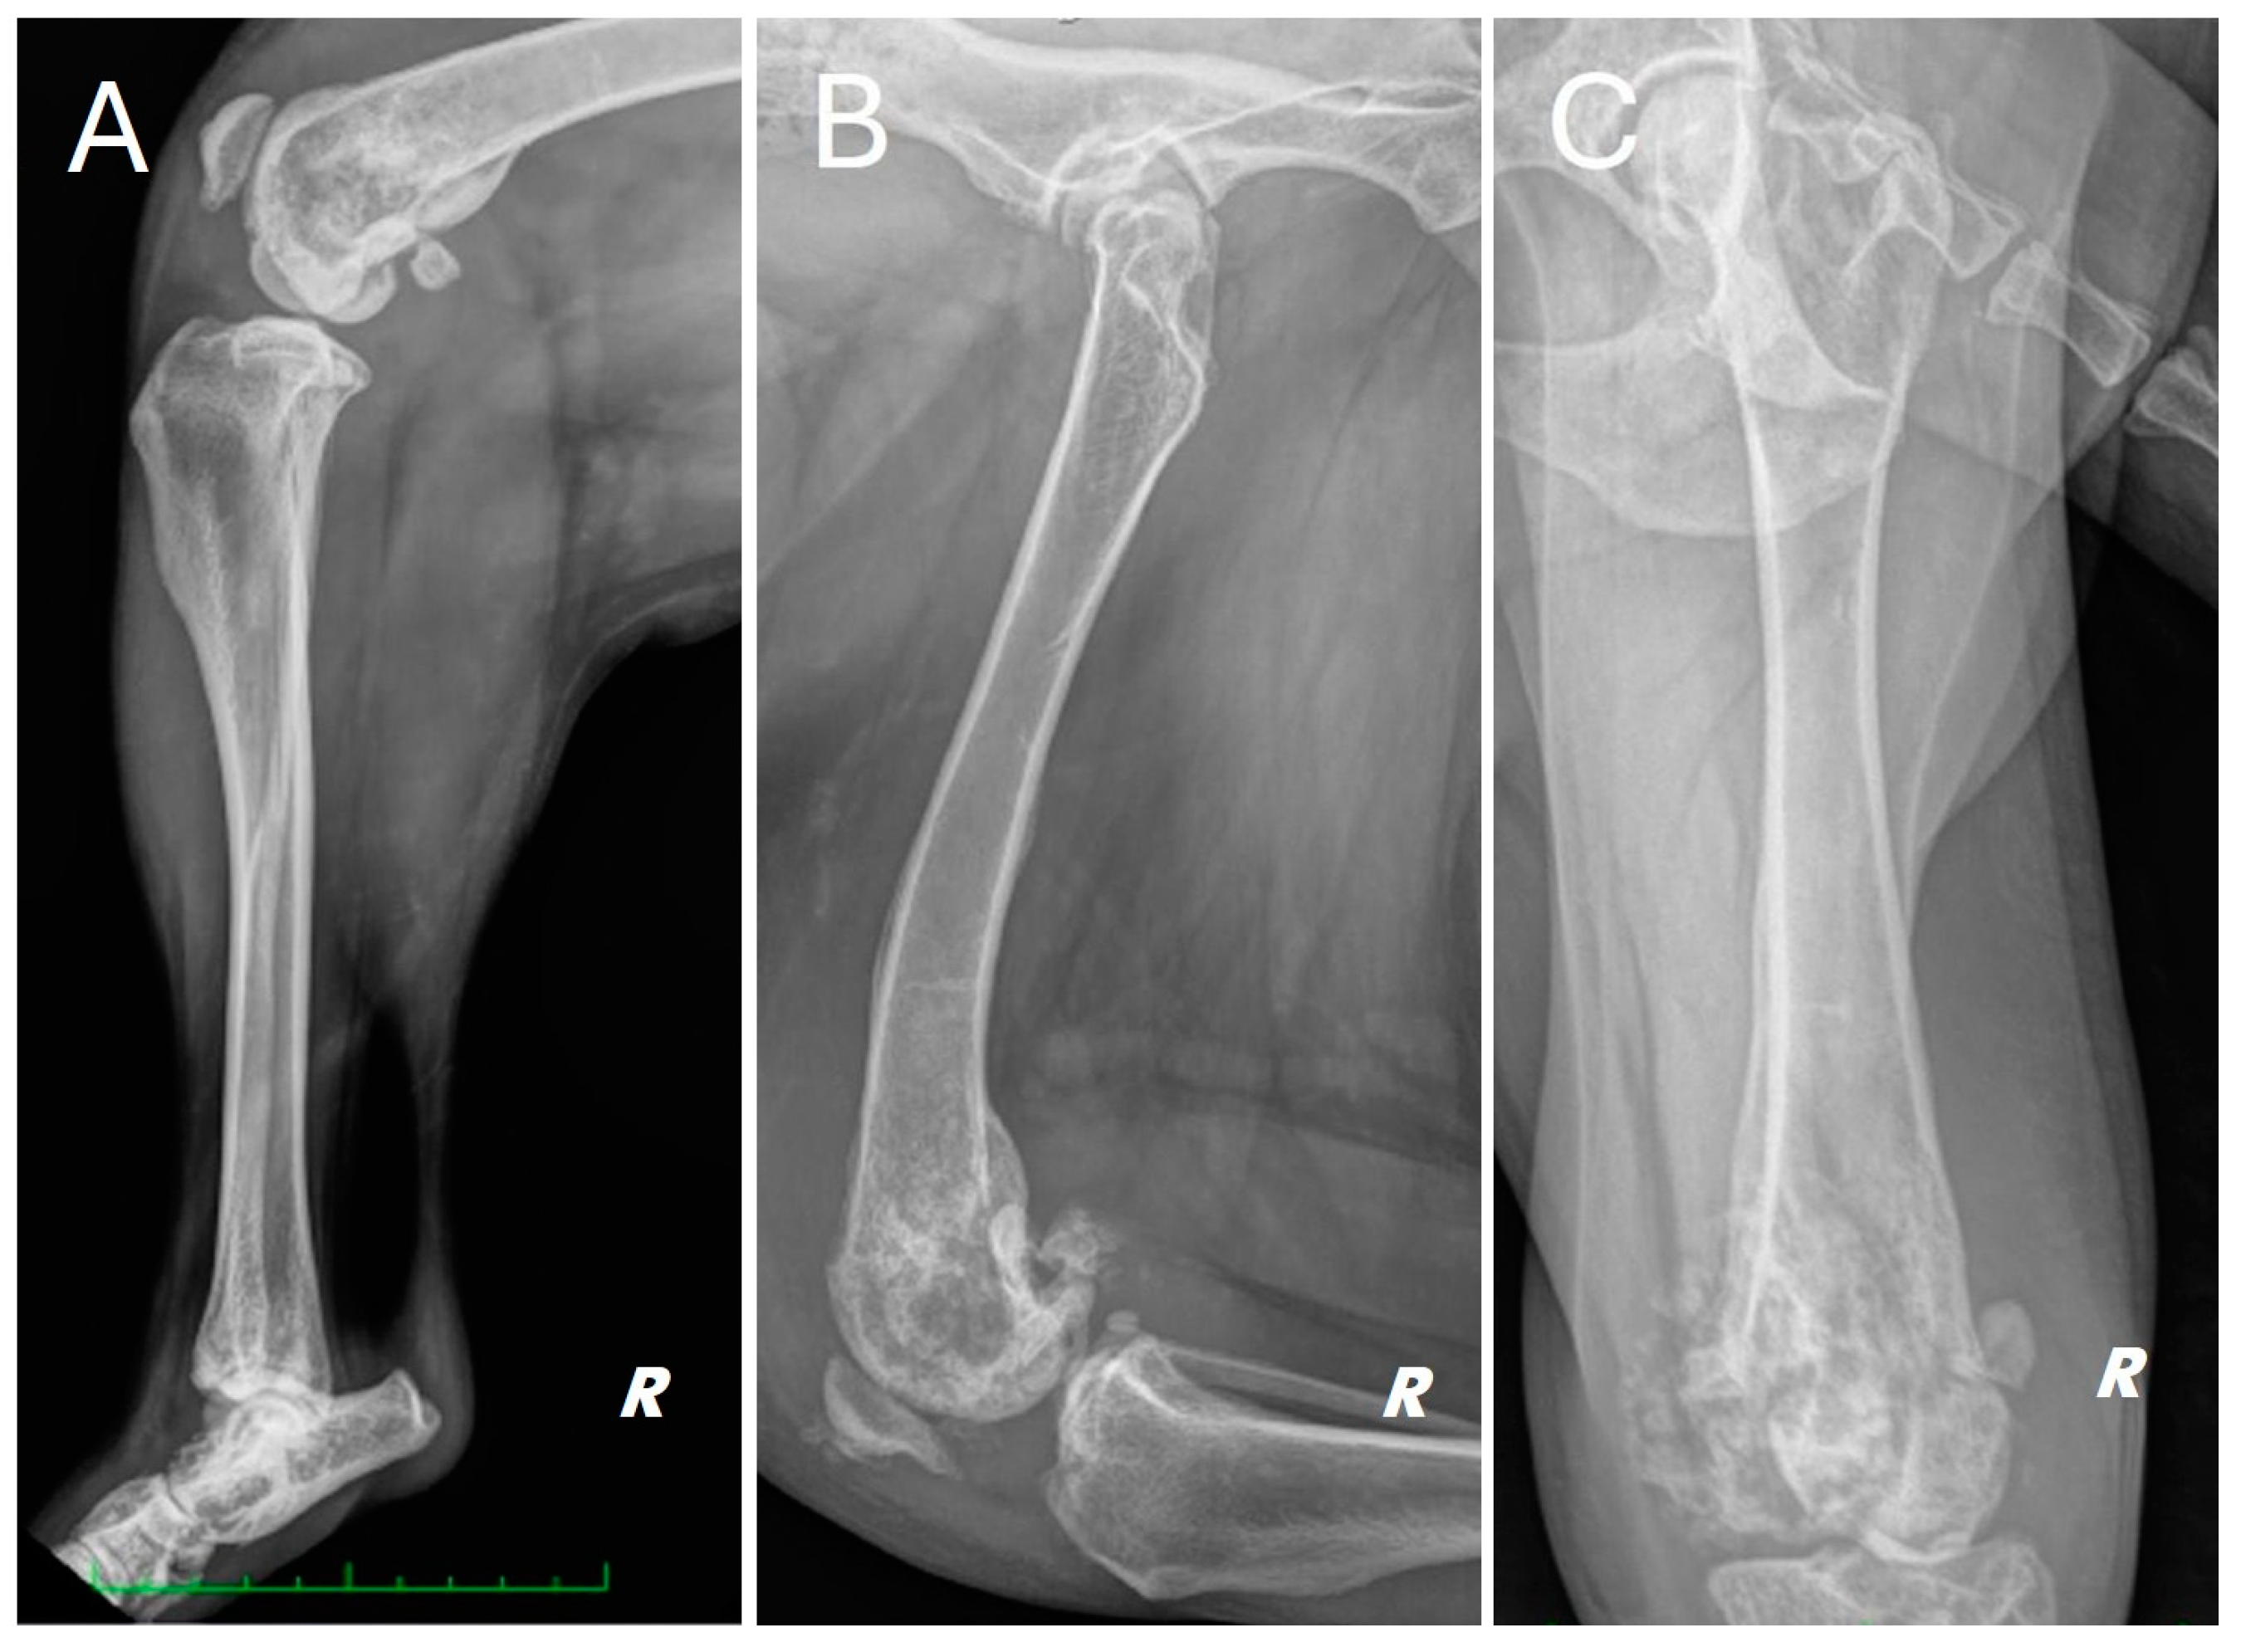

Radiographs of the right hind limb were taken in mediolateral and craniocaudal projections under sedation and analgesia (Figure 1).

Figure 1.

Different radiographic projections of the right hind limb. (A) mediolateral projection of the tibia, (B) mediolateral projection of the femur, (C) cranio-caudal projection of the femur. Structural and radiopacity alteration near the distal femoral end and the knee joint is repeated in all projections performed.

The radiograph showed evidence of osteoarthritis of the right hip joint with bone remodeling of the femoral head and neck. Significant structural changes were observed in the distal metaphysis of the right femur, with a marked “moth-eaten” pattern of bone lysis, pronounced and irregular periosteal reaction and extensive alteration of the normal pattern of the medullary canal in a disto-proximal direction up to the level of the middle third of the diaphysis. A complete, comminuted, slightly dislocated pathological joint fracture of the medial femoral condyle, osteoarthritis of the distal pole of the patella and marked joint and periarticular soft tissue swelling of the femorotibial–patellar joint were also found. Finally, there was moderate sclerosis and mild osteophytosis of the tibiotarsal joint.